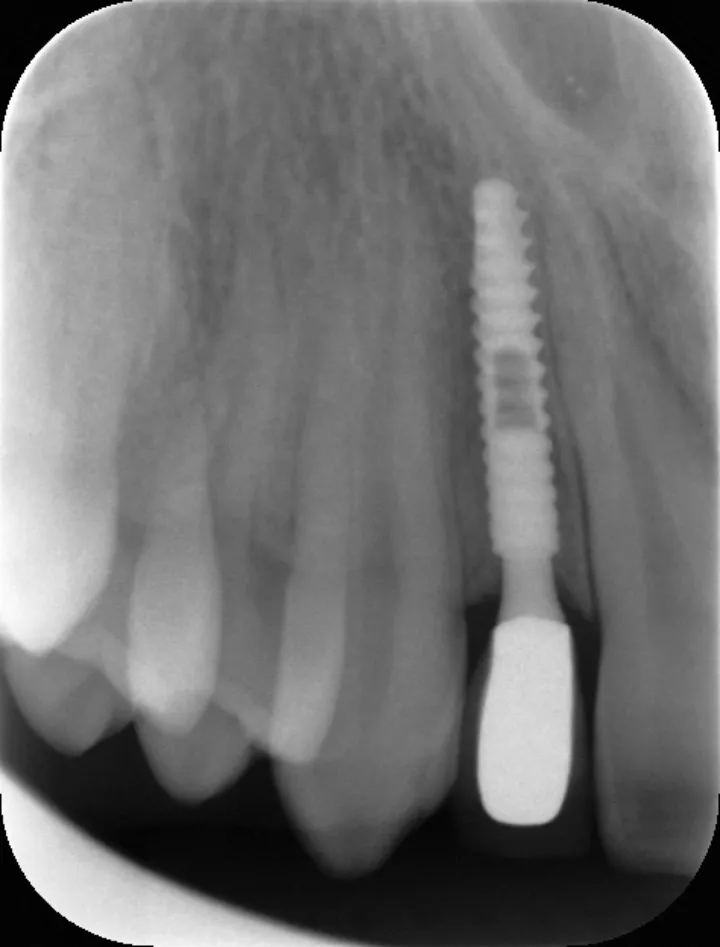

图 35 :术后 1 年随访 X 线影像。

图 48 :术后 1 年口内情况。

图 49 :术后 1 年随访 X 线影像。